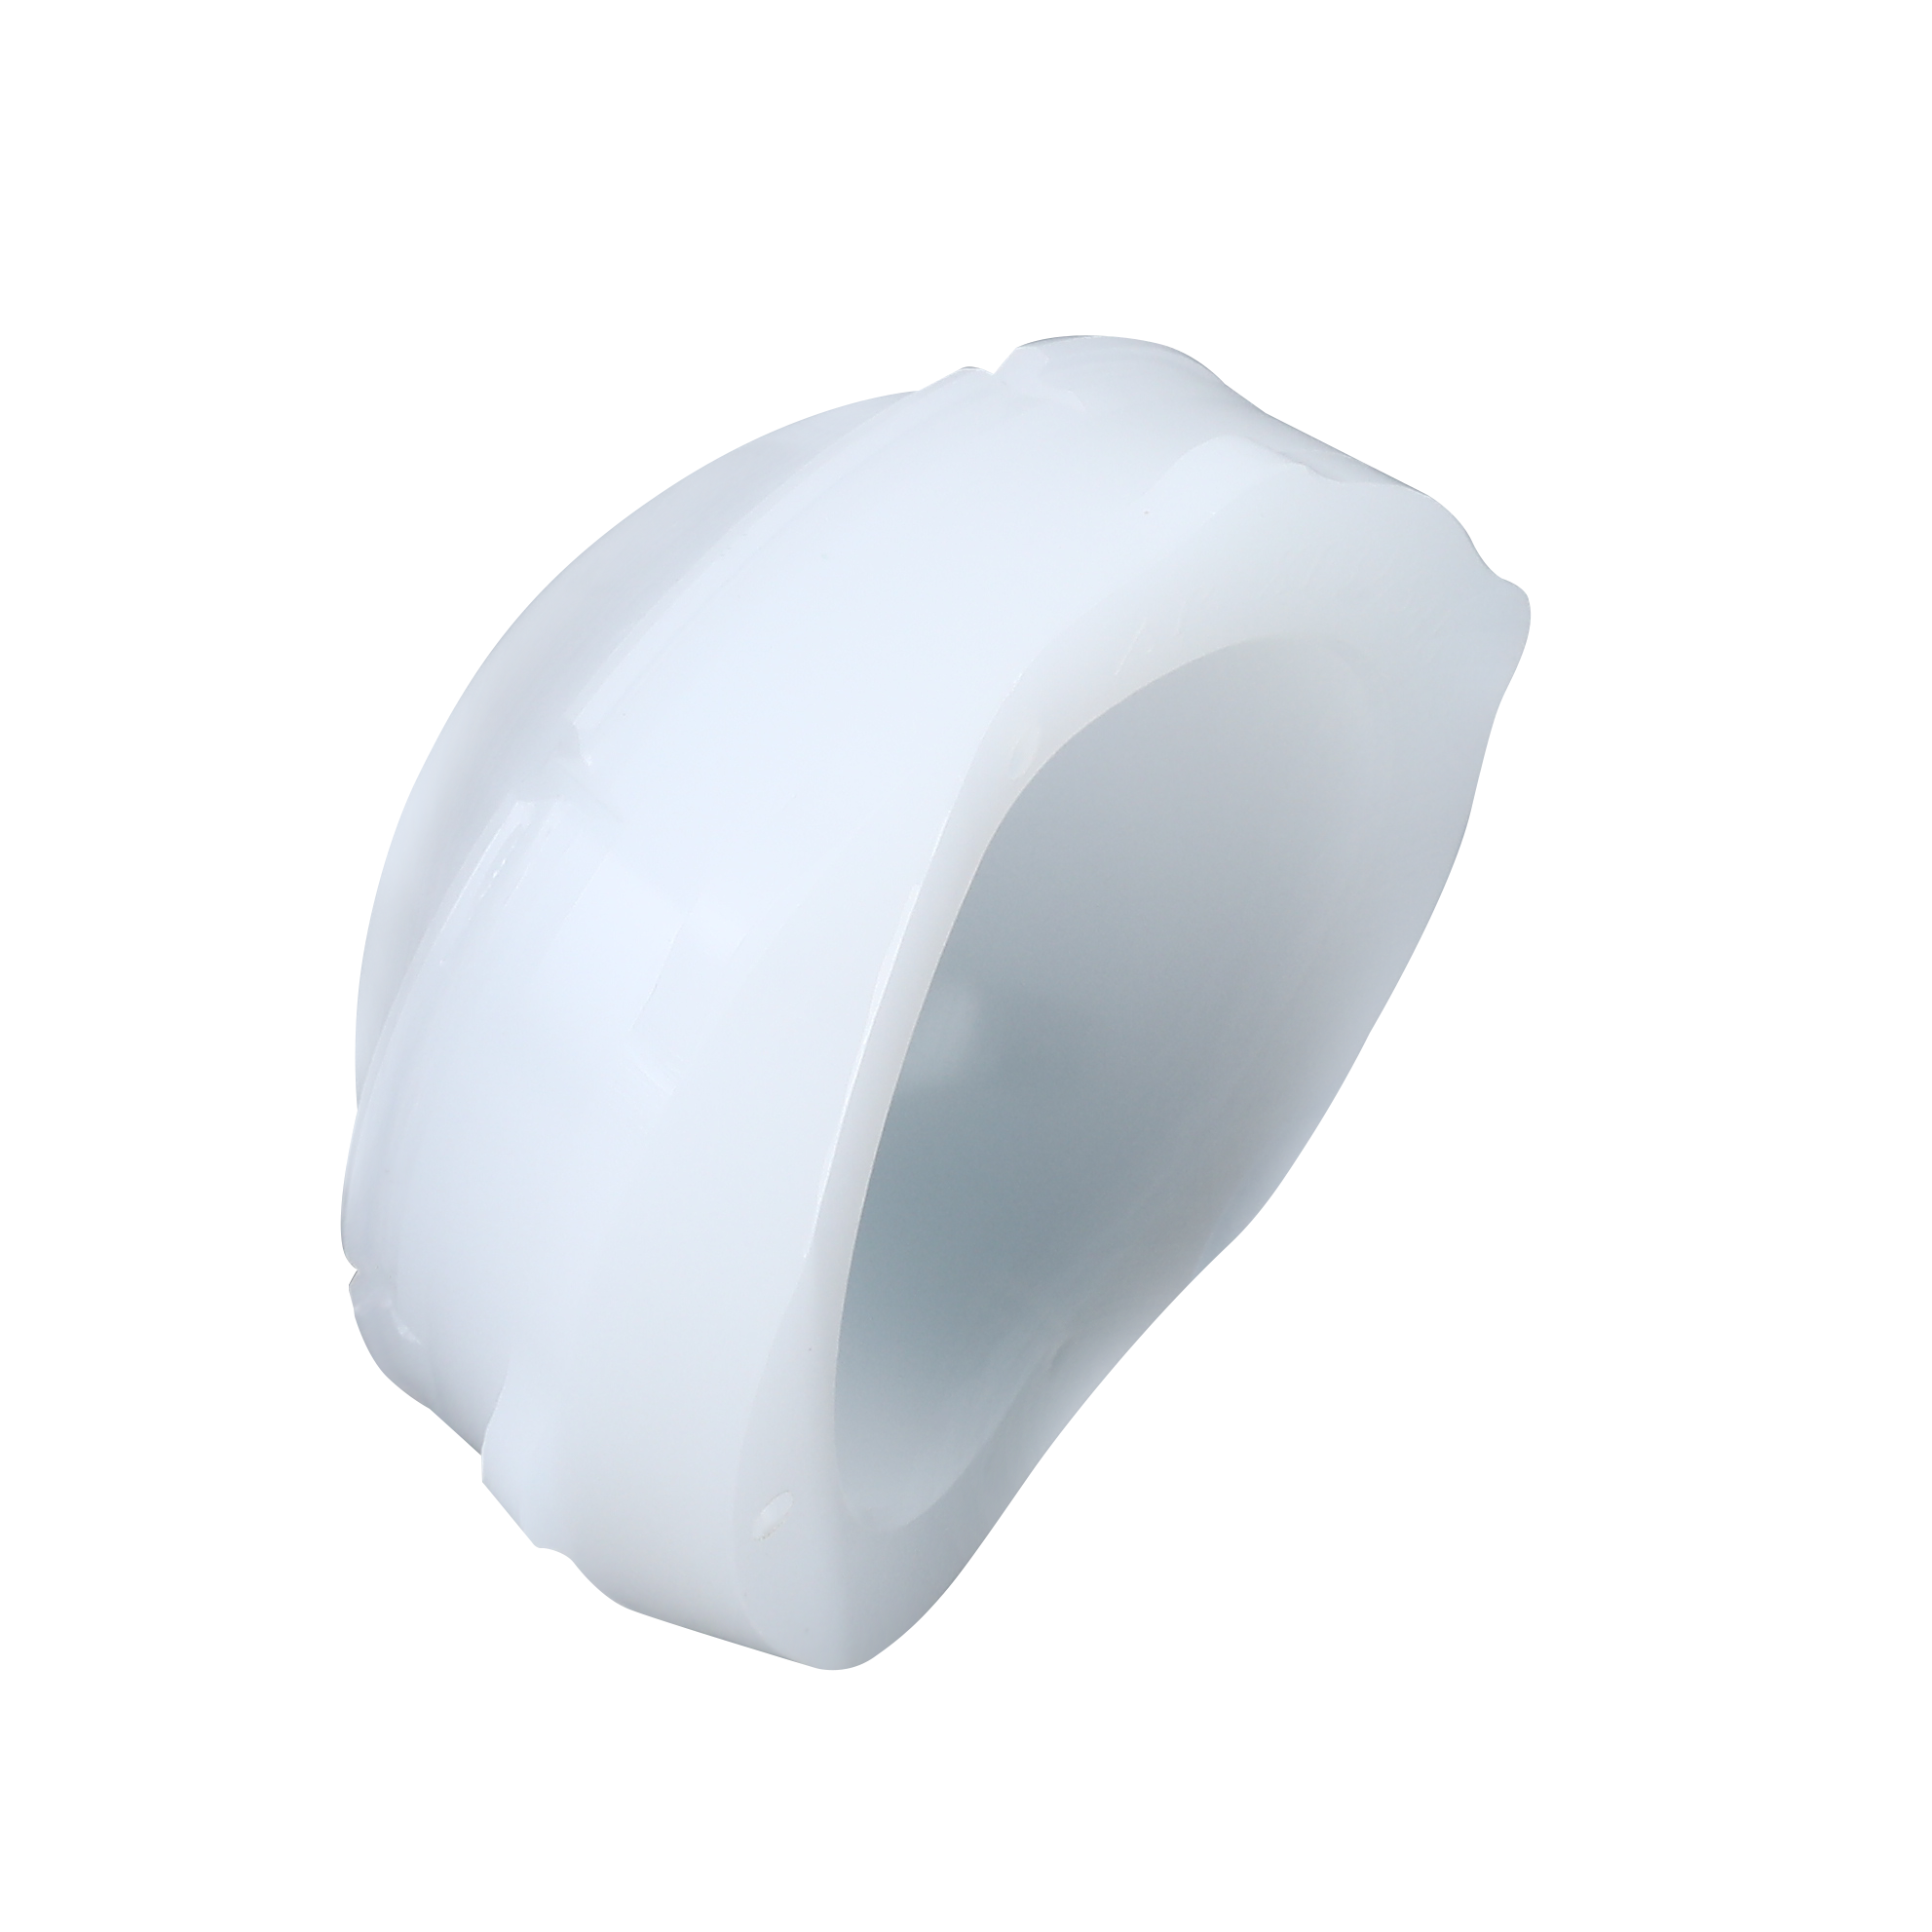

XE Acetabular Liner

Made of XLPE, as part of the STANDFIRM Hip Replacement System.